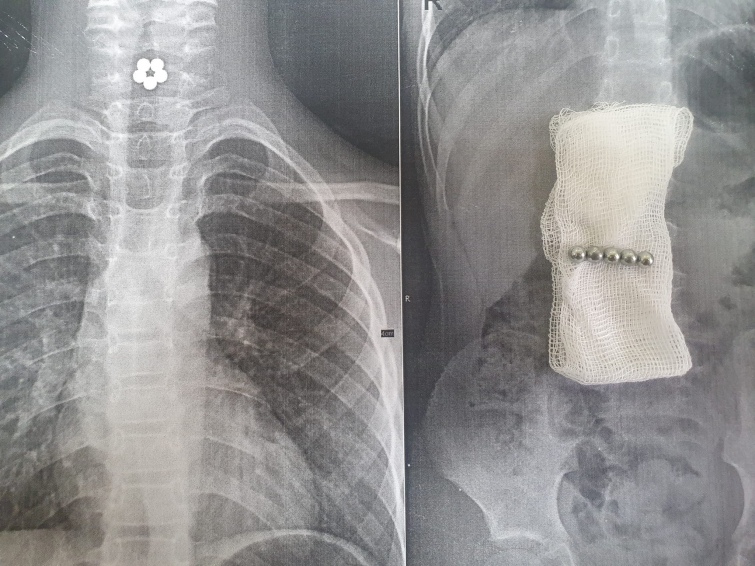

У Львові лікарі дістали зі стравоходу дитини магнітні кульки. Між собою вони утворили квітку.

Медики зазначили, що врятувати життя 7-річній дитині вдалось через те, що магніти не встигли опуститися до кишківника.

“Батьки невідкладно відреагували на скарги дитини та погіршення самопочуття. Вони викликали швидку допомогу, коли дівчинка почала задихатися та скаржитися на дискомфорт в області шиї”, – йдеться у повідомленні.

Лікарі в "Охматдиті" зробили рентген та терміново почали операцію.

Вони пояснили: якби кульки спустилися до кишківника, то це могло б порушити цілісність його стінок.

За допомогою новітнього обладнання та під контролем оптики, магніти дістали.